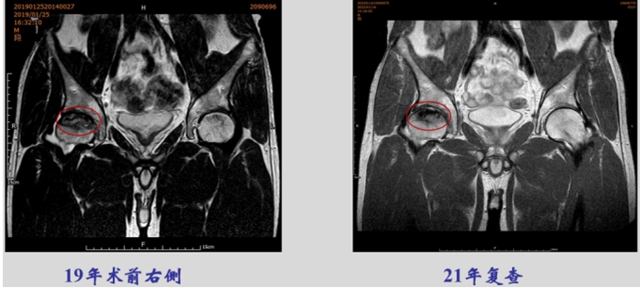

治疗3月,王先生已经无疼痛症状,基本实现自由行走,2年后复查,坏死塌陷区域已重新出现新骨,这颗股骨头真正的死而复生。